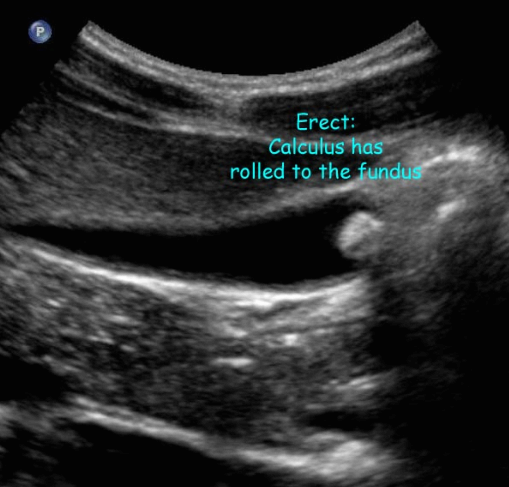

- 환자 체위에 따라 움직임 (rolling stone sign)